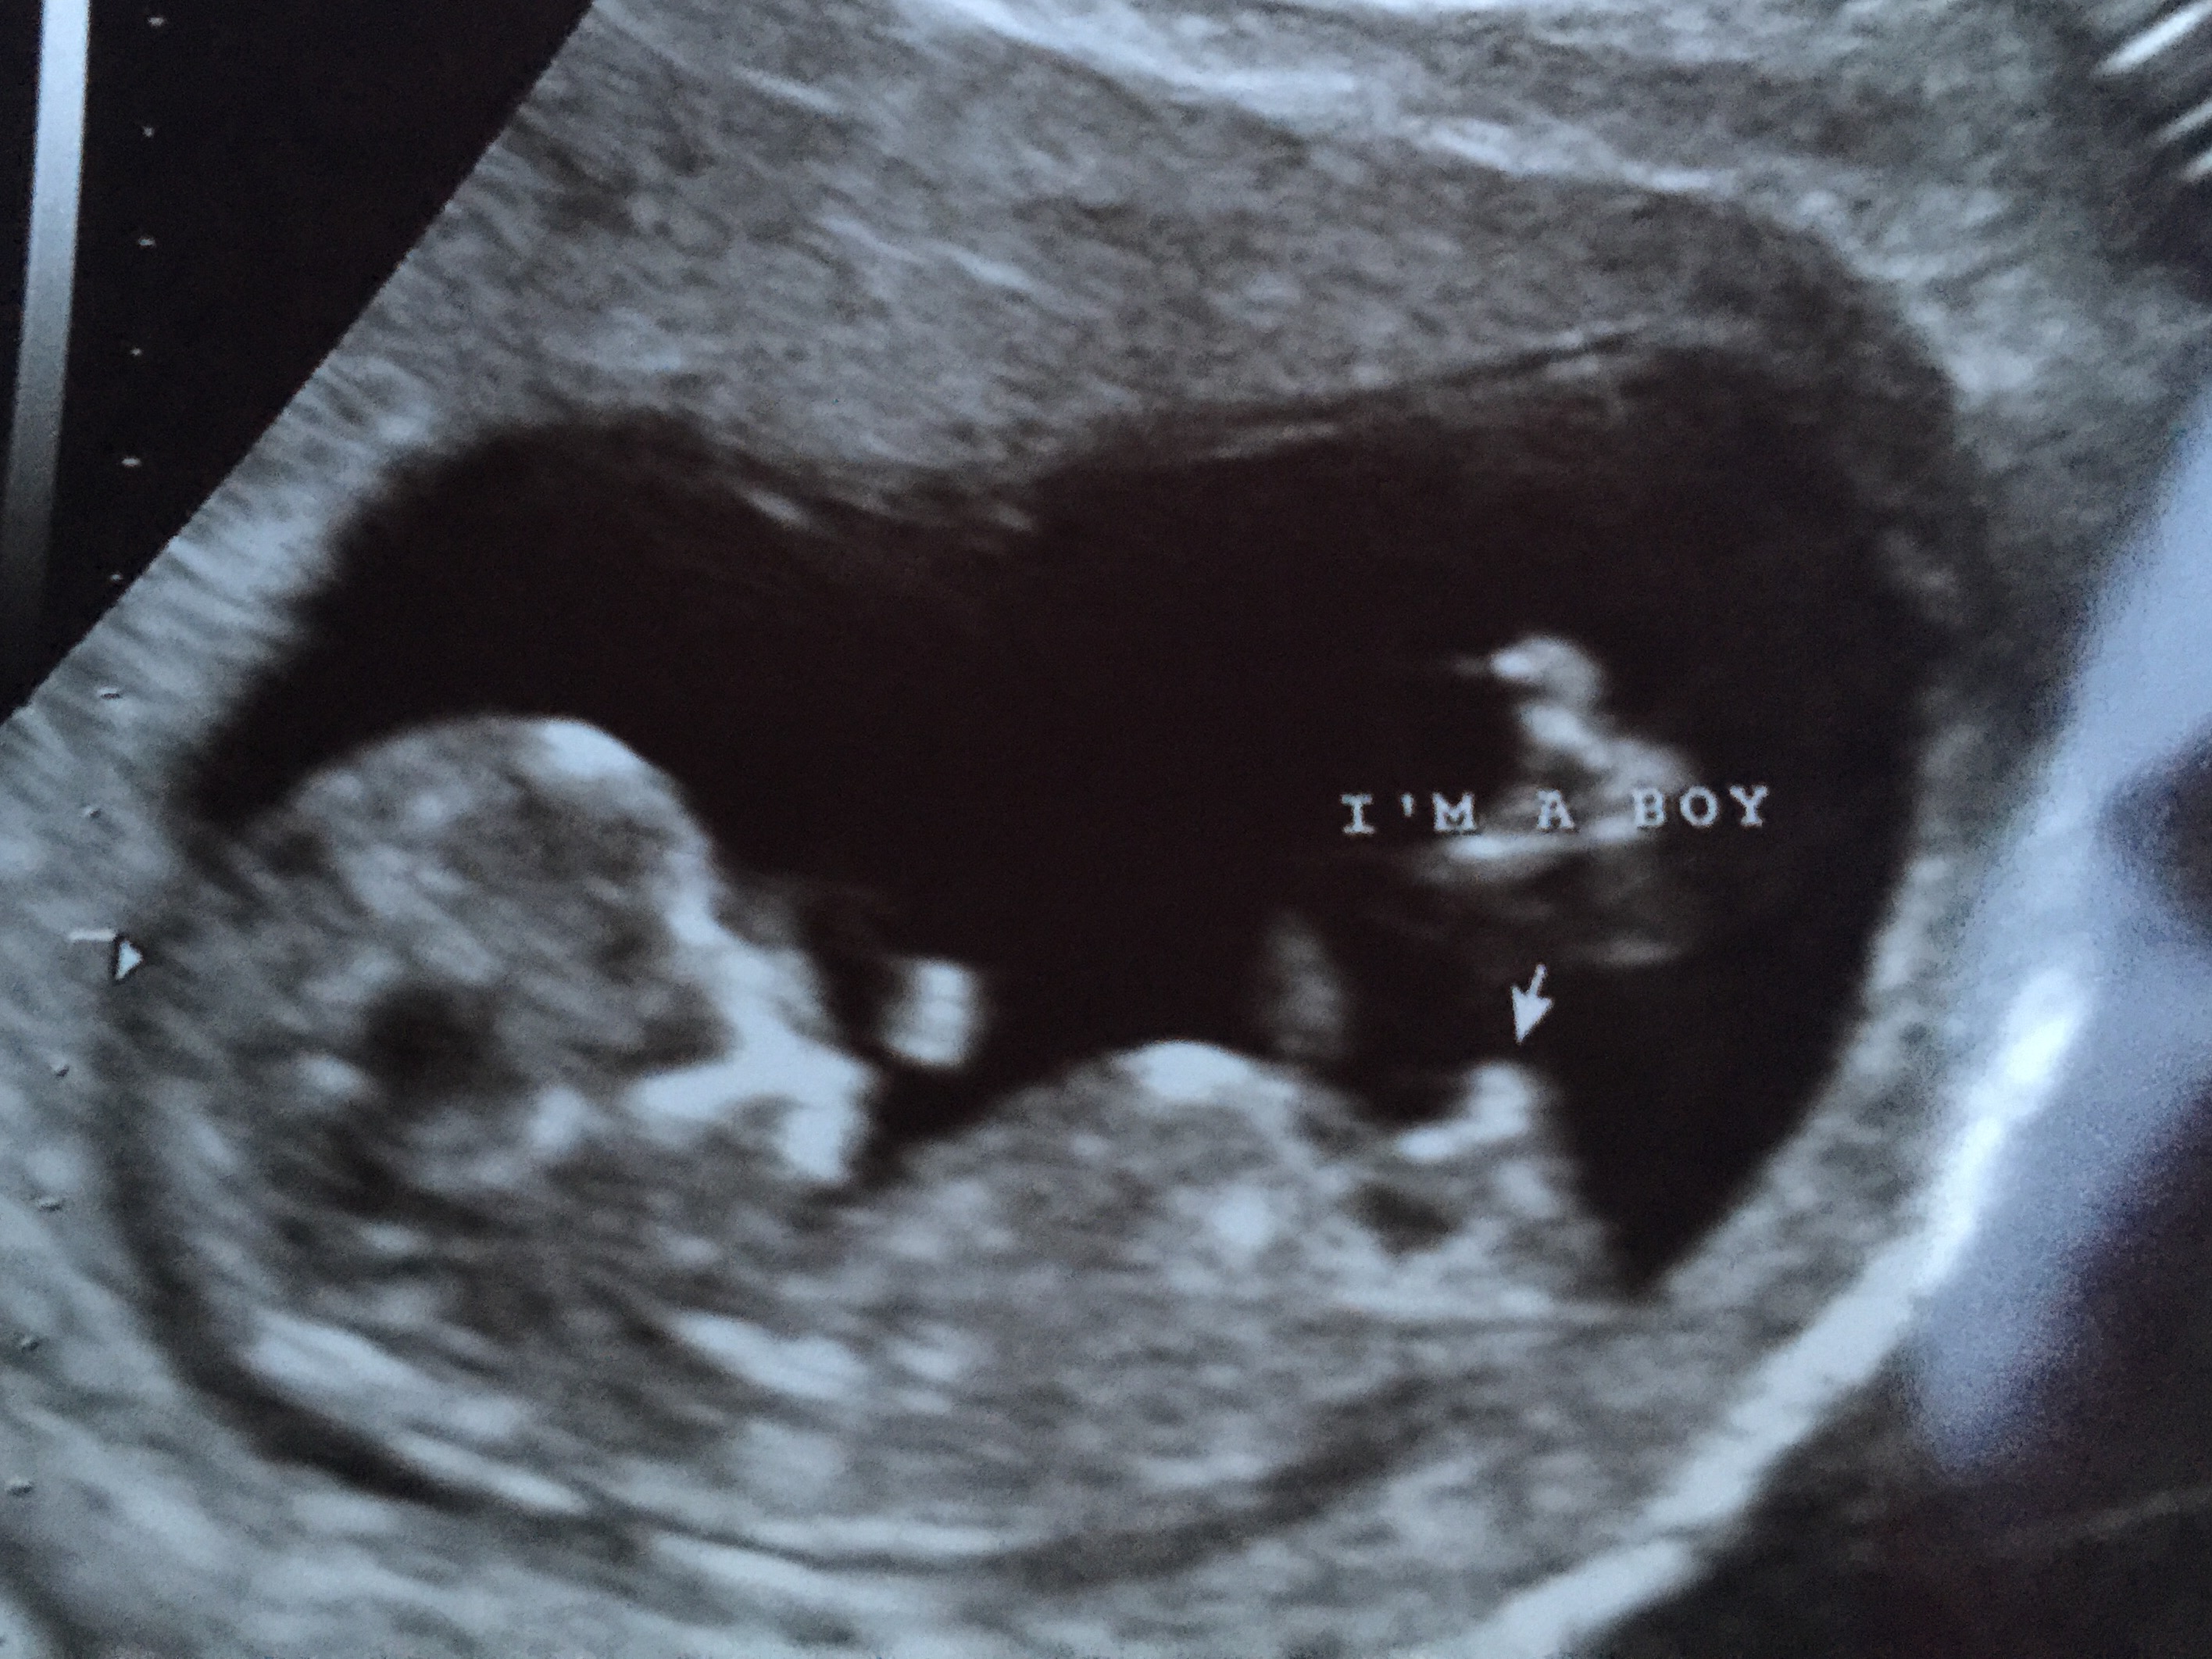

Six days ago at 11+1 I was so sure I was having a girl the tech even said 90% sure today at 12+0 she told me she was 96% sure it's a boy! So over the moon! Hoping she's not wrong Attachment 31341

congrats on your little man